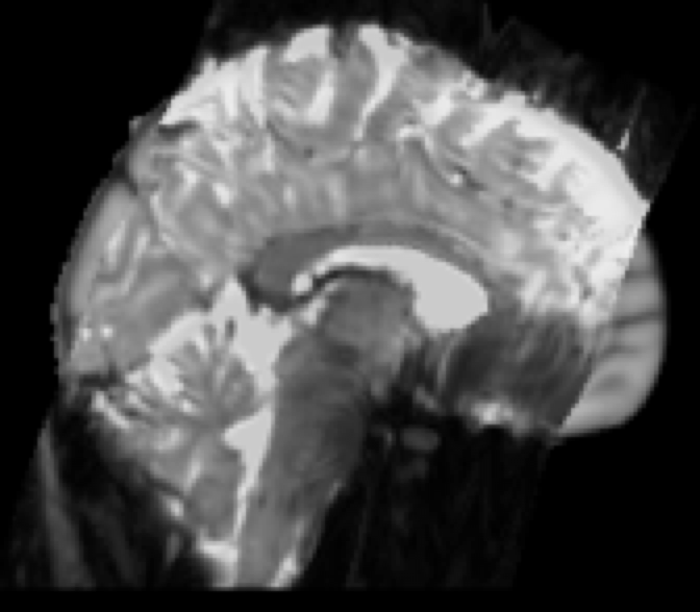

Example result: EPI (functional) resampled to standard space

Partial FOV FMRI Registration

- Partial field of view functional images: An additional step is inserted prior to step 1. A whole-brain functional scan with identical parameters (resolution and slice orientation) to the partial FOV needs to be acquired, and a limited (3 degrees of freedom) FLIRT registration is conducted from the partial FOV to whole-brain functional image.

Example result: Three-stage registration

Partial FOV EPI to Whole-brain EPI to T1 Structural to Standard Space

Example result: Partial FOV EPI (functional) resampled to standard space